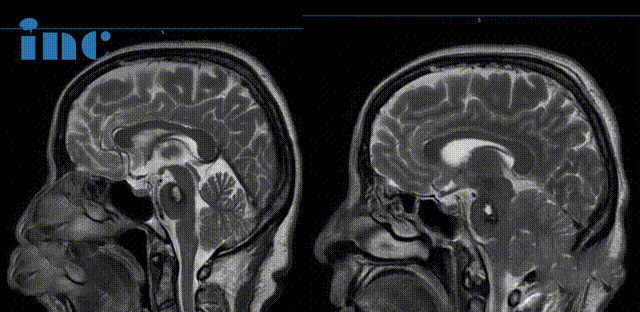

▼術(shù)前及術(shù)后1天影像對比

術(shù)前及術(shù)后1天影像對比

腦干海綿狀血管瘤影像

影像對比提示金女士的海綿狀血管瘤增大,出血量逐漸增多